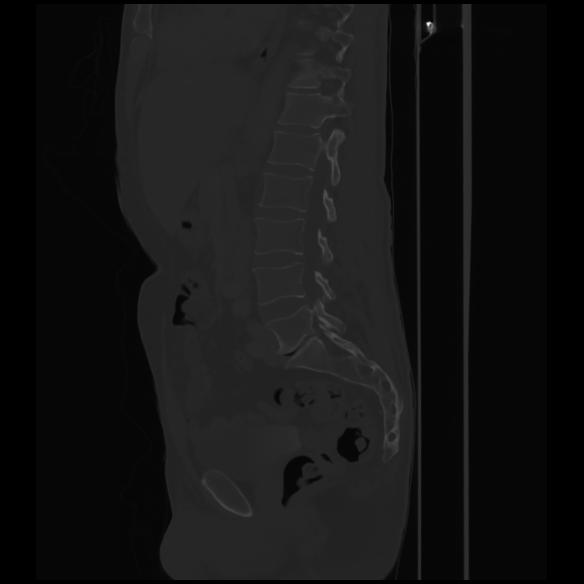

7 CUERPO,CE,Sagittal,3.000,CUERPO,Sagittal,